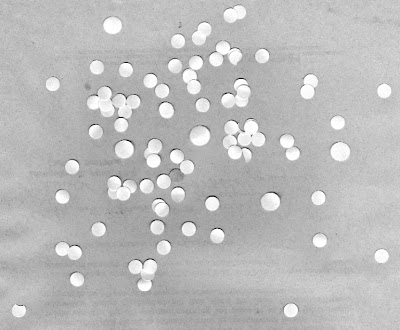

and this an image of normal cells with larger cancer cells

|

| normal cells with cancer cells |

With this, we may now look for cancer cells! Using the fact that the average area of a normal cell is ~ 444 pixels, we can make a circle with the same size and use this as strel to process the image of normal with cancer cells. First we binarize the image,

|

| Binarized image of normal cells with abnormally large cancer cells. |

Then, use the opening operation with the circular strel,

|

| Applying the opening operation on the binarized image. |

Do you see the cancer cells now? There are only 5 of them, but still too many normal cells here. Let's see if applying the opening operator again can remove these.

|

| The opening operation applied twice. |

Now there's the five cancer cells with two outliers. Not bad. :D